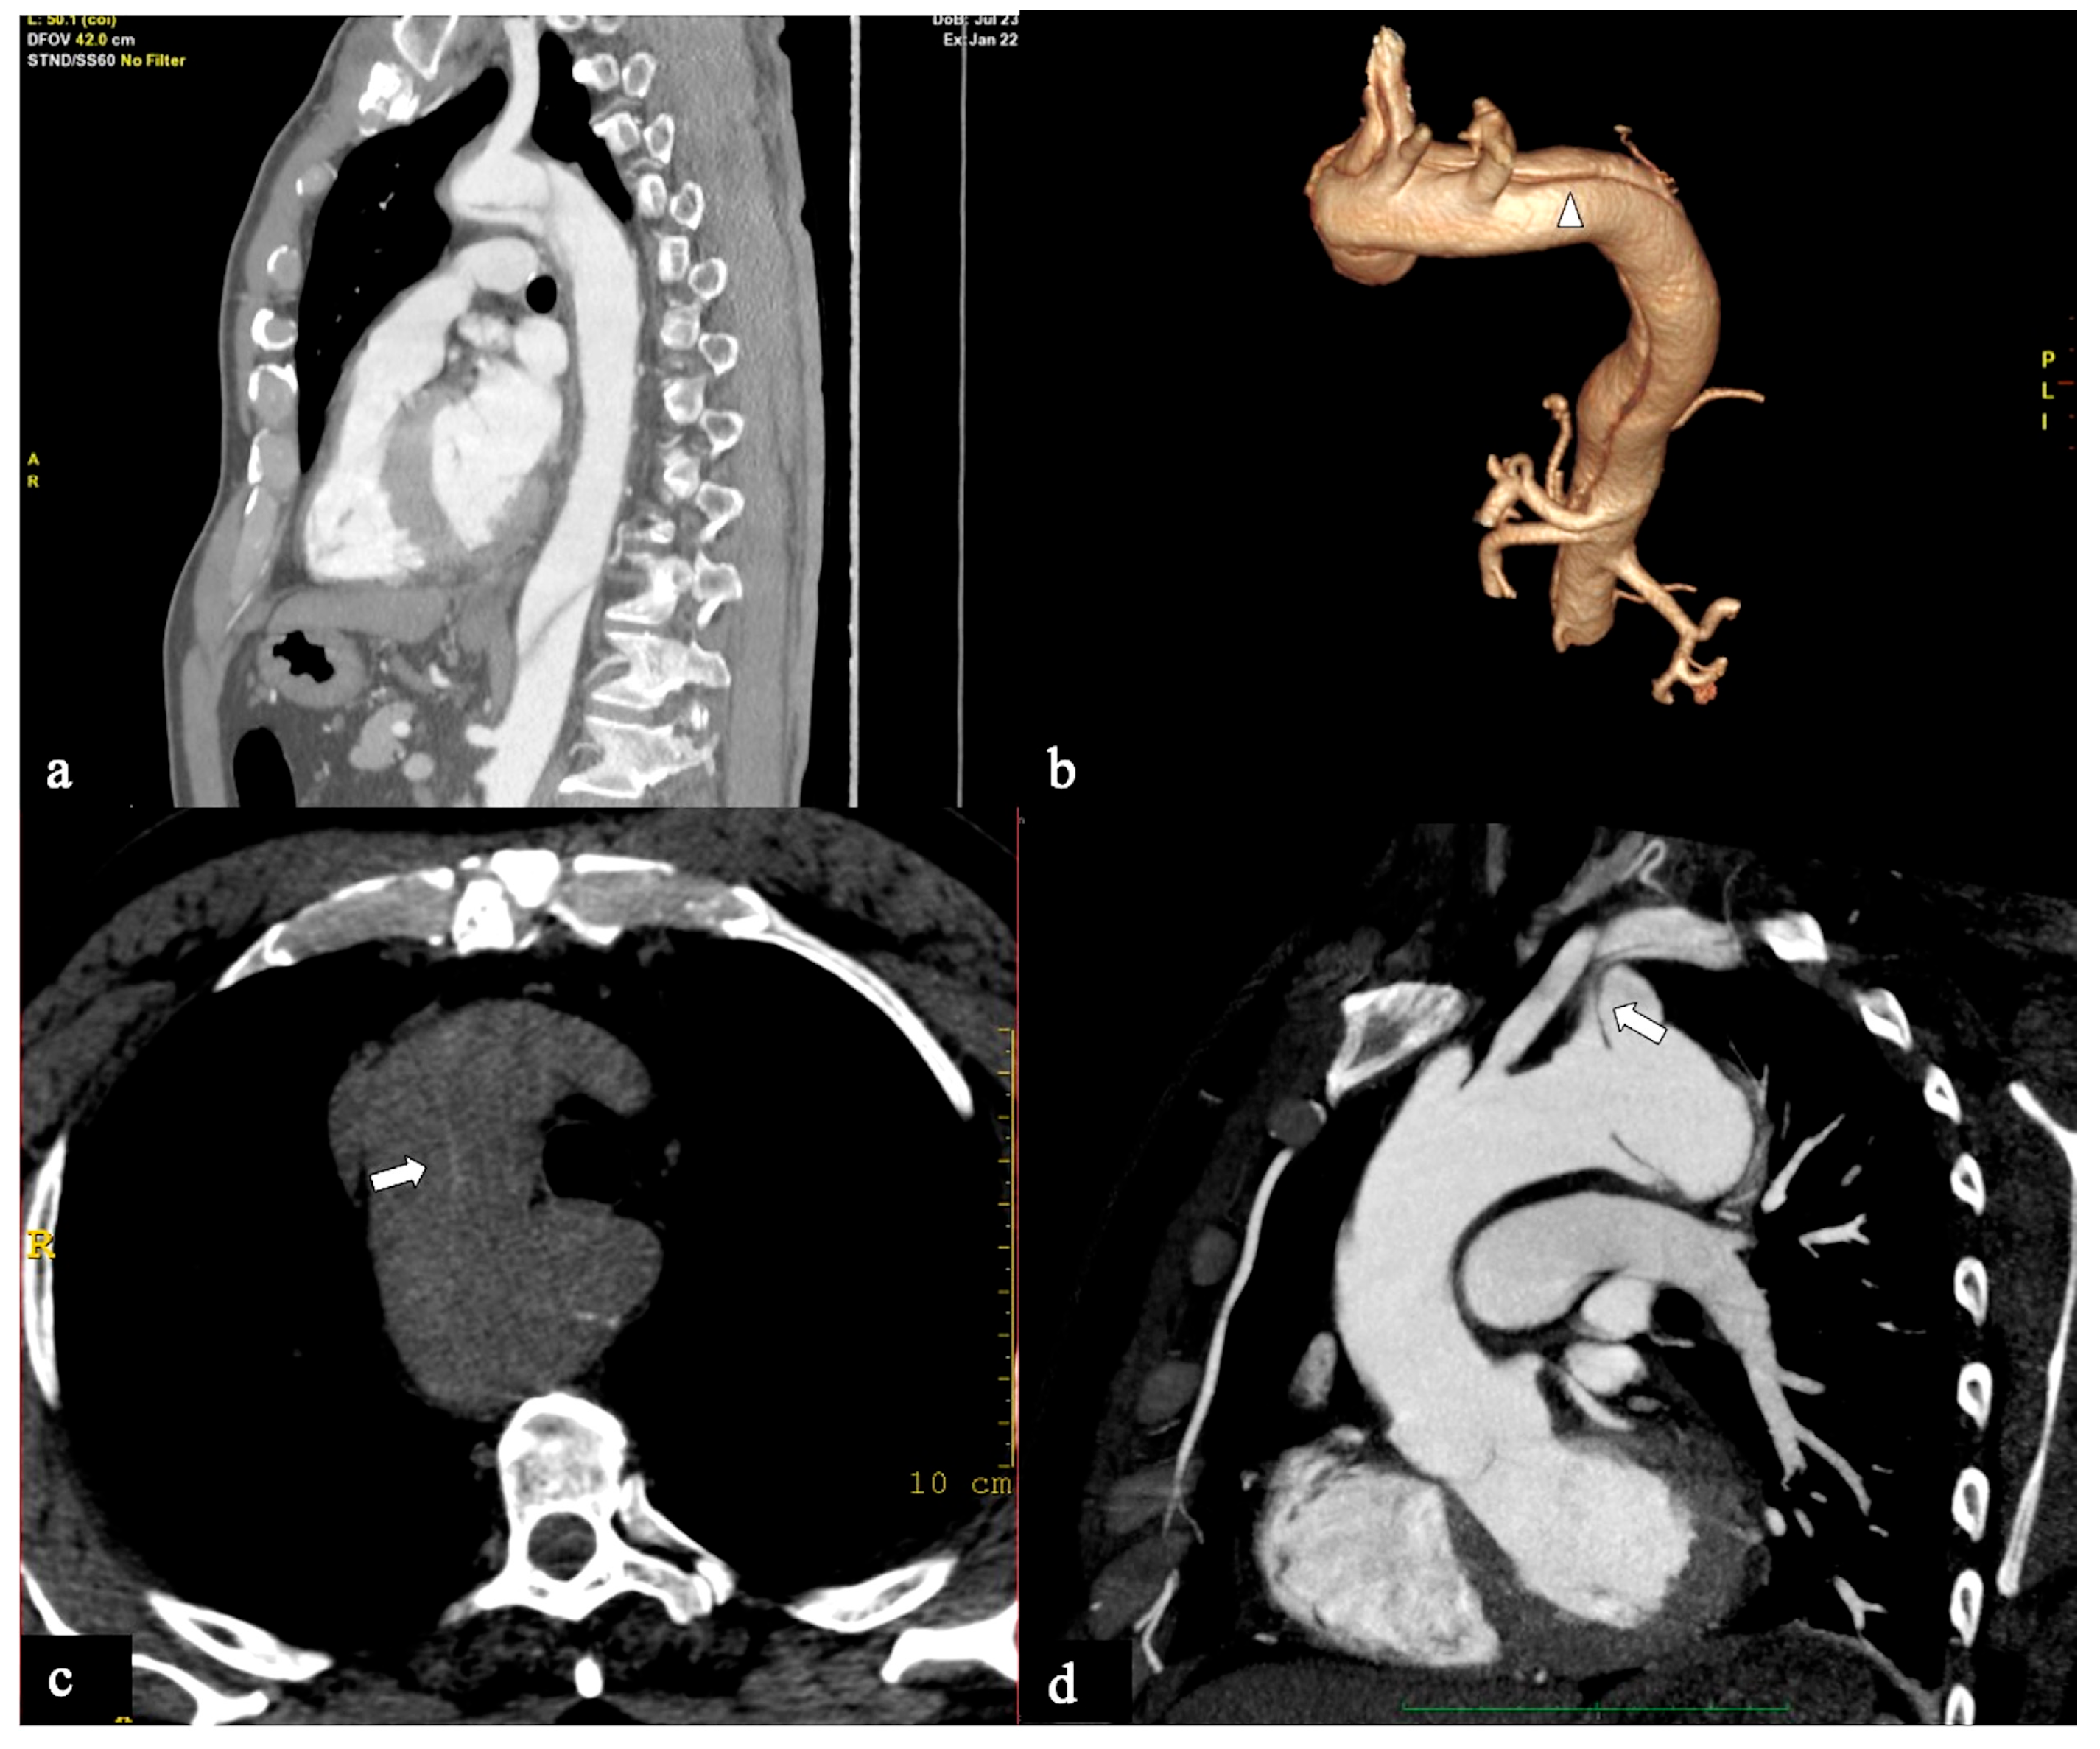

- In Configuration 3 (Arch entry), the primary ET is situated within the aortic arch, and the flap extends into the DTA without affecting the ascending aorta [38]. This Configuration 3 occurred in 7 (19%) patients (Figure 5a,b). This AD configuration was already described as proximal type B dissection according to 2010 AHA guidelines [7] and recently reported as arch B group AD from IRAD [38] and as non-A non-B acute AD with entry tear in the aortic arch [39,40]. In this configuration, the ET was often located in the greater curvature of the arch (4/6), while in one case (1/7) its location was not clearly identified. In total, 4/7 of these patients underwent hybrid and 2/7 surgical therapy.